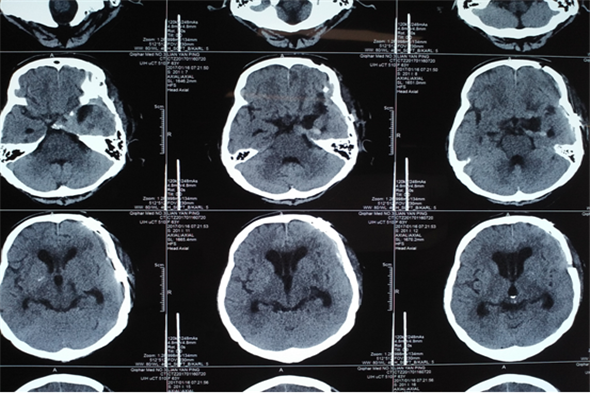

当日,先由麻醉医生为患者麻醉,在手术室护士的密切配合下,由吴卫东主任为患者施行手术,术中吴卫东主任凭借精湛的手术技能,在开颅切除蝶骨脊旁5.0cm肿瘤后,在狭小的动脉与各个神经缝隙间精细操作,以刮匙完全刮除鞍内肿瘤,保留周边血管及神经,手术进行的十分成功,在术后的第一天患者就意识清醒,无功能缺失。

垂体瘤在临床出现症状较多,主要是肢端肥大,巨人症及库欣氏综合征,亦可出现泌乳或性功能低下等症状,垂体瘤从形态上可分为:微腺瘤、大腺瘤、巨大腺瘤。超过3cm即为巨大腺瘤,该患者肿瘤直径为5cm,为巨大腺瘤。其周围为颈内动脉,视神经及动眼神经等重要组织结构,手术风险较大,神经外二科成立以来垂体瘤切除术已是常规手术,但此巨大垂体瘤实属罕见。吴卫东主任精准的判断及娴熟的手术技巧,神经外二科团队及麻醉科快速、高效的配合再一次创造了奇迹。

术后CT